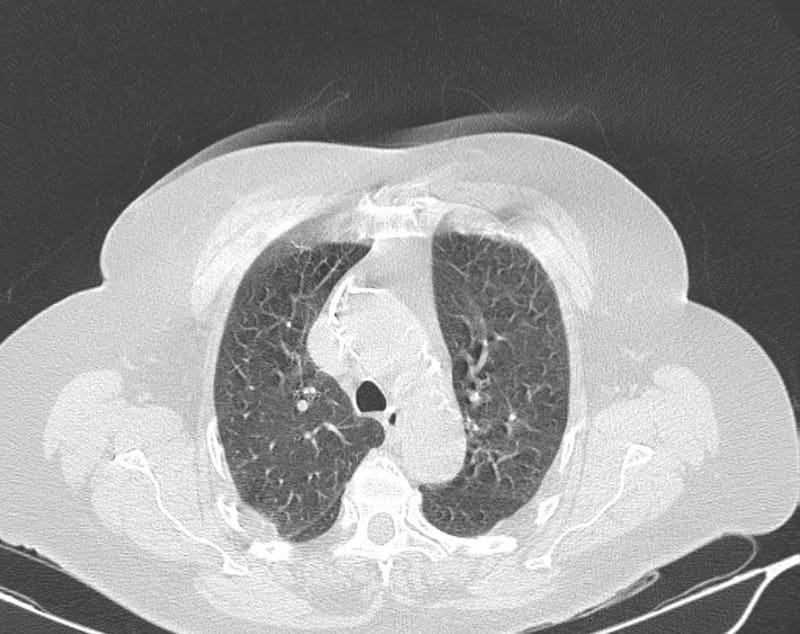

Ronald Reid, broncopulmonar y médico jefe del Servicio de Medicina de Clínica Universidad de los Andes, señala que el daño a los pulmones por el coronavirus tiene dos fases. “Primero, una fase inflamatoria muy importante, en la cual el virus produce un daño directo a nivel de las células del epitelio, que es el tejido que cubre los alvéolos o los bronquios. Eso finalmente produce una cascada inflamatoria, que hace que los alvéolos se llenen de líquidos con células inflamatorias, se ocupe el espacio e impide que puedan funcionar".

“Es decir, lo primero que se ve es una neumonía, que es con características de tipo inflamatoria, y eso produce una falla respiratoria severa y los pacientes pueden caer en ventilación mecánica o cosas así”, explica Reid.

“Todo el material inflamatorio que produce el coronavirus, va generando áreas de infiltración e inflamación en el pulmón, y finalmente toda la unidad se va rellenando de un material inflamatorio dado por elementos solubles y también por células que van obstruyendo el flujo y van generando los síntomas”, explica Beltrán.

Reid señala que luego viene una segunda fase, que se establece en período inflamatorio. “En la gran mayoría de los pacientes se empieza a reabsorber, se va limpiando el pulmón, al igual que como cuando una persona tiene una infección en un dedo. En principio el dedo se hincha y después se deshincha, pasa lo mismo en este caso”.

"Sin embargo, hay algunos pacientes en que esta inflamación puede evolucionar hacia fibrosis, donde se produce una cicatriz, y esa zona del pulmón se empieza a retraer, el tejido normal del pulmón se reemplaza por tejido fibroso cicatrizado. Eso puedo dejar un daño secuelar respiratorio”, explica Reid.